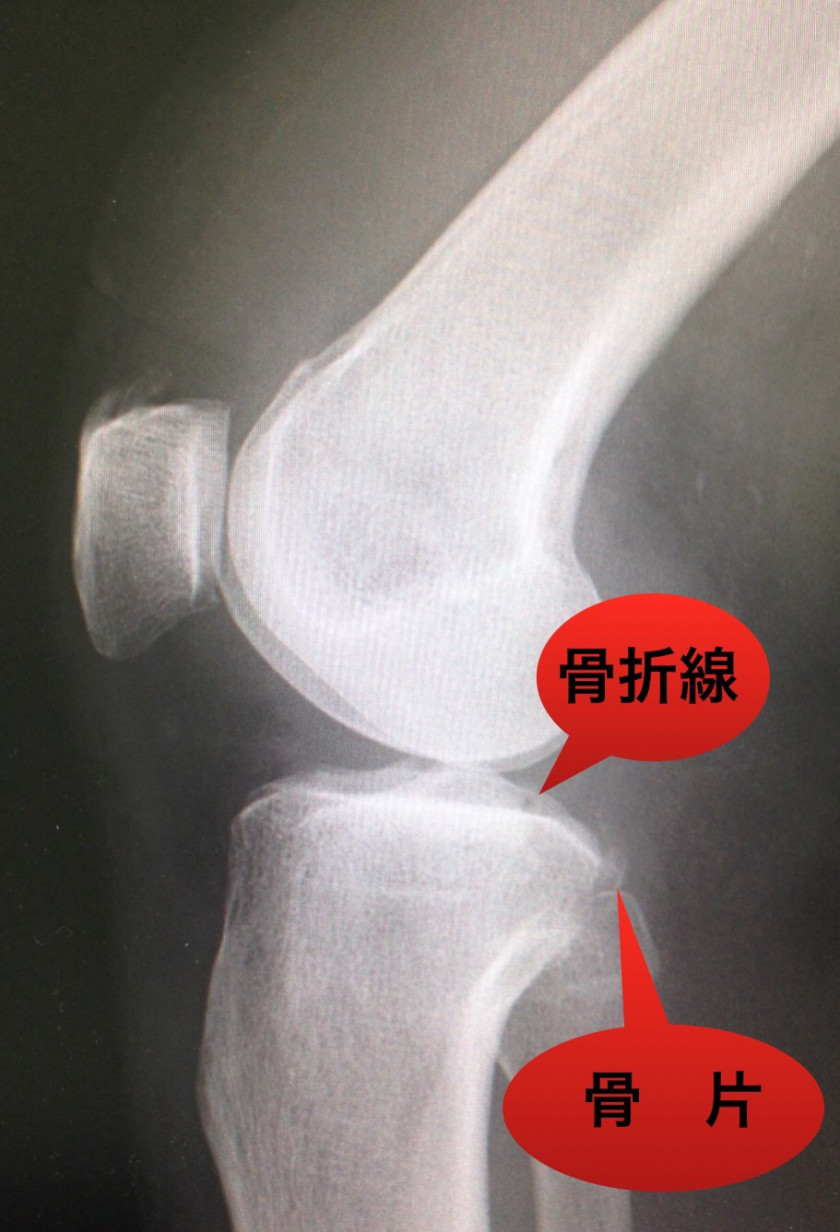

先日、骨折部治癒を確認できた患者さん。もう、この方の外来診療も、開業する前からだから・・・10年以上になります。年末に転倒しそうになり、膝を踏ん張り、カラダを支えた際に受傷。

右膝痛を主訴に年始早々受診されました。触れば明らかな関節の腫脹あり。「ン・・・(イヤな予感)。」たいてい、当たるイヤな予感。

レントゲン撮影すれば骨折確認‼️患者さんの膝 正常な状態での同部位で比較して下さい‼️

右の写真のどこに異常ありですか❓ 診断は以下の通り、靭帯の付着部を中心に損傷しています。最近では、臨床上も膝不安定性なく、疼痛も改善、レントゲン上も骨癒合確認。現在、日常生活に支障なく、歩行できています。

先日、骨折部治癒を確認できた患者さん。もう、この方の外来診療も、開業する前からだから・・・10年以上になります。年末に転倒しそうになり、膝を踏ん張り、カラダを支えた際に受傷。右膝痛を主訴に年始早々受診されました。触れば明らかな関節の腫脹あり。「ン・・・(イヤな予感)。」たいてい、当たるイヤな予感。